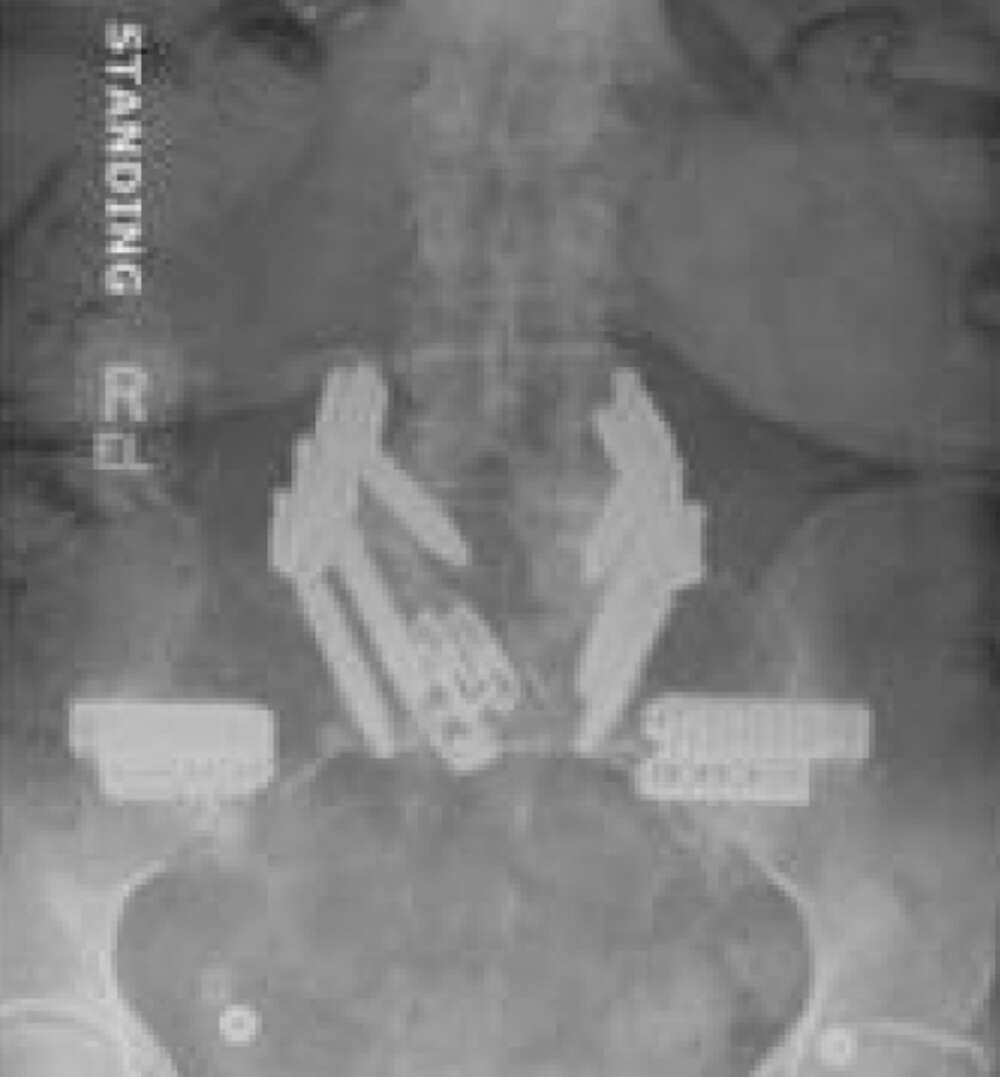

- Bi-lateral SI joint degeneration with pain post revision surgery verified via SI joint block injection.

Surgical Procedure:

- Bilateral SI joint fusion using the iFuse 3D™ Implant System, August 2020

Post-op:1

- Post-op resolution of bilateral SI joint pain.

- CT of lumbar spine at +2 years post-op shows confirmation of the SI joint fusion.

Inline dennis 02